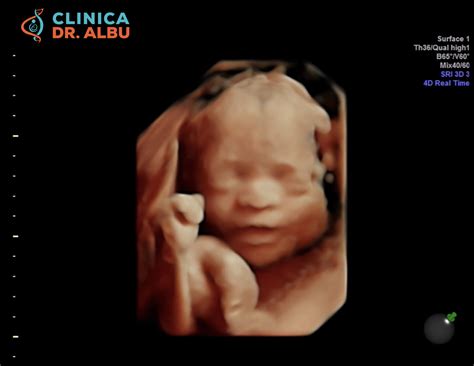

- Examinarea ecografică (ecografia de morfologie fetală de trimestrul I): Această ecografie permite vizualizarea unor caracteristici ale fătului, cunoscute sub numele de "soft markers", care pot sugera prezența unor probleme cromozomiale. În cadrul acestei examinări se măsoară lungimea cranio-caudală (CRL) pentru a confirma corect vârsta gestațională și se evaluează translucența nucală (NT), o măsurătoare a lichidului acumulat în zona cefei fătului.

Parametrii Ecografici

- Translucența Nucală (NT): Această măsurătoare a lichidului din spațiul subcutanat posterior al gâtului fătului este un indicator important. O NT crescută în primul trimestru poate fi asociată cu un risc mai mare de anomalii cromozomiale. Valorile normale ale NT variază, în general, între 0.5 și 2 mm.

- Osul Nazal: Vizualizarea osului nazal fetal în intervalul 11-13+6 săptămâni de sarcină este un alt parametru evaluat. Absența osului nazal în această perioadă a fost corelată cu un risc crescut de sindrom Down (aproximativ 69% dintre feții cu sindrom Down pot prezenta această caracteristică) și alte aneuploidii.